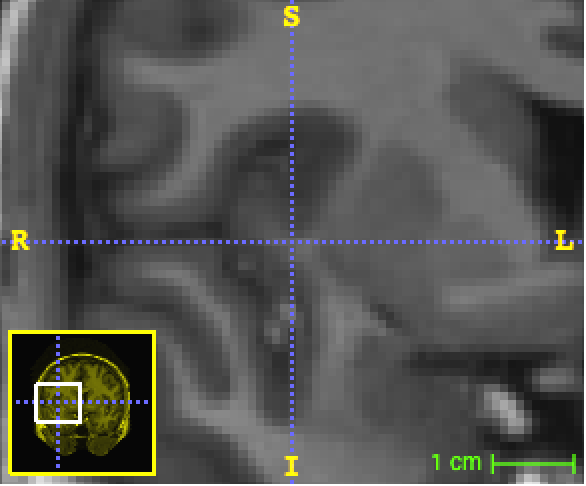

Refer to caption

(a) 29×29292929\times 29 patches (b=29𝑏29b=29).

(b) 87×87878787\times 87 original patches downscaled into 29×29292929\times 29 patches (c=29𝑐29c=29, s=3𝑠3s=3).

Figure 4: Example of random 2D patches from the MICCAI dataset.

We set out to study the performance of SegNet on this dataset despite the fact that deep learning techniques generally require much larger training datasets. All computations had to be run in-memory using a single NVIDIA Tesla K40 GPU with 12GB memory. Therefore we faced a trade-off between the number of datapoints and the number of dimensions of the dataset. On the basis of initial tests, we decided to extract randomly and uniformly across the brain a sample of approximately 202020k voxels from each one of the 151515 atlases, for a total of 300300300k voxels for training purposes, which amounts to only approximatively 1.5%percent1.51.5\% of all the available voxels in the dataset. For each voxel, we extracted a 737773777377-dimensional input vector consisting of a 3D patch of 133superscript13313^{3} voxel intensities (a=13𝑎13a=13), three 2D orthogonal patches of 292superscript29229^{2} voxel intensities (b=29𝑏29b=29), three 2D downscaled patches of size 292superscript29229^{2} containing averaged voxel intensities (the original patch width is 878787 and the scale is 333, i.e. c=29𝑐29c=29, s=3𝑠3s=3) and 134134134 distances to centroids. Figure 5 shows a sample of 2D patches. A validation dataset consisting of 404040k data points was also extracted from the the 15 atlases.